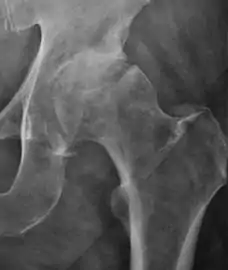

Plain radiography allows us to categorize the hip as normal or dysplastic or with impingement signs (pincer, cam, or a combination of both). Besides these, pathologic processes like osteoarthritis, inflammatory diseases, infection, or tumors can also be identified (Figure 1).[1]

Figure 1.

Radiography in normal hip

X-ray in pincer impingement type of hip dysplasia

X-ray of cam

Hip in osteoarthritis

Septic arthritis

X-ray in pediatrics